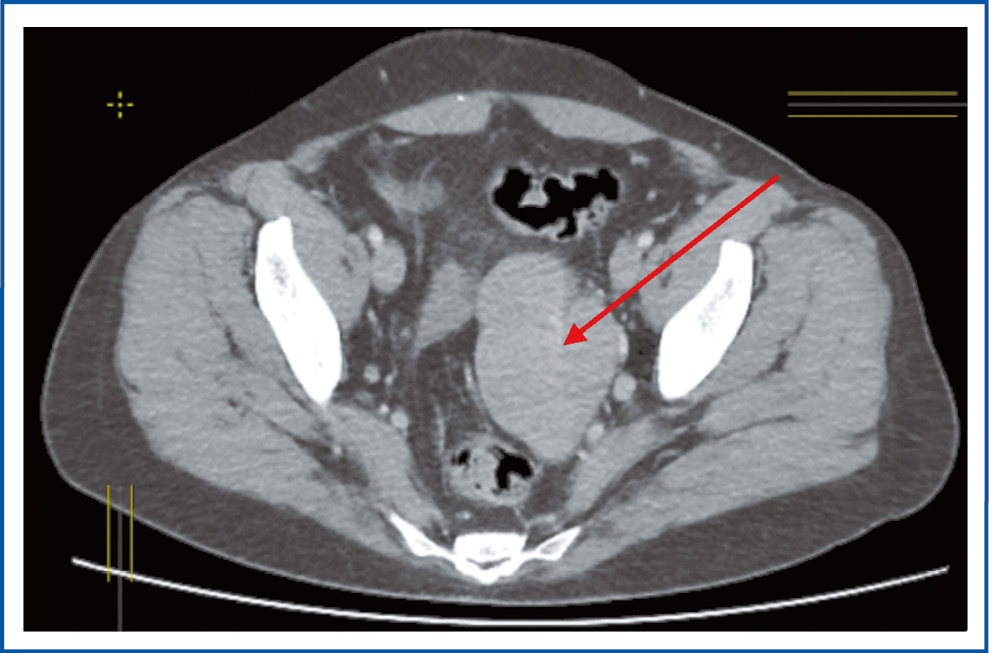

Через 6 лет, в мае 2022 г., пациентка снова обратилась в ГУЗ ОКОД г. Ульяновска, при осмотре – жалобы на боли в животе умеренного характера, слабость. При обследовании по данным мультиспиральной компьютерной томографии (МСКТ и КТ) с контрастным усилением выявлено наличие однородного многоузлового новообразования слева в ЗБП 7×5×8 см с интенсивным накоплением контрастного вещества (рис. 2), множественные образования печени, лимфатические узлы (ЛУ) ворот печени – до 14 мм (рис. 3), 2 образования в легких: 1 – в верхней доле левого легкого, 1 – в нижней доле правого легкого (рис. 4, 5).

Рис. 2. МСКТ. Стрелкой указано новообразование в ЗБП.

Fig. 2. Multispiral computed tomography (MSCT). The arrow indicates the neoplasm in the abdominal space.